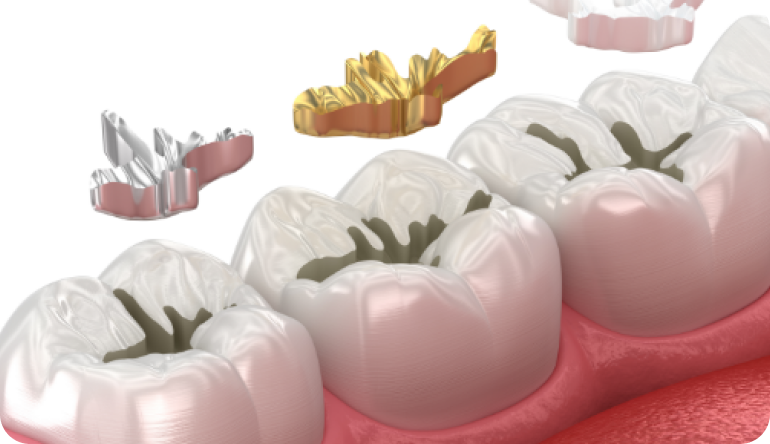

턱관절치료

턱관절치료

턱관절치료

턱뼈와 두개골을 연결하는 관절의 통증 및 기능 장애 해결을 위하여 구강학적 접근으로 물리적, 약물적 치료를 병행합니다.